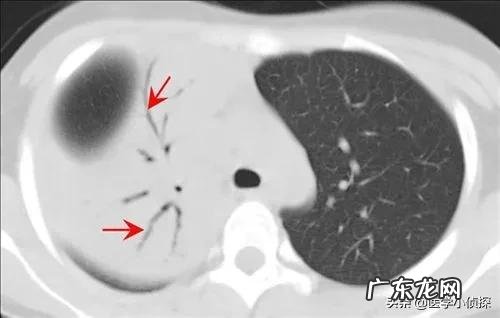

先讲一下大家最为熟悉的肺结节 。首先 , 大家要记住 , 一般我们说的肺结节 , 指的都是≤3cm以下的结节 , 对于超过3cm的结节 , 我们就不再叫它结节了 , 而是称之为肿块 。

而且拍片发现肺结节 , 本身不能说我们得了什么病 , 因为肺结节只是我们影像学上的一种表现 , 并不代表这个结节具体会是个什么东西 。只是对于我们正常人来说 , 不应该有结节 , 因此结节的出现肯定代表我们的肺部有病变 , 但具体它是什么 , 是良性的 , 还是恶性的 , 需要进一步的来区分 。只不过 , 一般情况下 , 在影像下我们统称这些都叫肺结节 。

而同样 , 我们既不知道它是个什么东西 , 也不知道它是怎么来的 , 有一部分人可能跟我们的肺部炎症有关;而有一部分可能与肺结核有关 , 但具体一个人为什么会长肺结节 , 目前并没有研究清楚 , 这就导致了很多在看到自己体检报告肺部有结节时候会有点恐慌!

假如你胸部CT检查出肺结节 , 重点关注报告单上这些内容 , 基本上不用过于担心肺结节最后会发展为晚期肺癌!